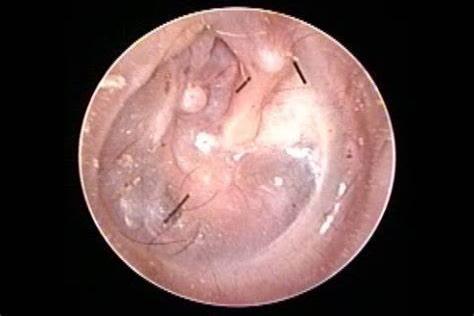

3、内层:粘膜层,与鼓膜粘膜相连。鼓膜穿孔后,外上皮层和内粘膜层可以再生,但中间层没有再生能力。松弛的鼓膜缺少中间层。

1、保护作用:鼓膜在外耳道和中耳之间,可以保护中耳和内耳。如果出现鼓膜穿孔,可能会引起急性中耳炎。严重者可能引起内耳感染,引起听力下降、耳鸣、眩晕。